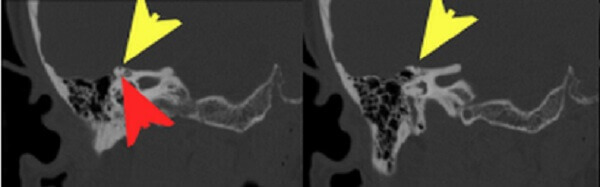

Diagnosis: Dehiscence of the right superior semicircular canal

Figure 1: Coronal reformats from a temporal bone CT (using a bone reconstruction algorithm with thin sections through the right internal auditory canal) demonstrate absence of bone (yellow arrow) covering the roof of the superior surface of the semicircular canal (red arrow). This finding is pathogmnemonic for dehiscence of the superior semicircular canal.

This is best appreciated on the reformatted images from an internal auditory canal protocol CT – coronal and semioblique, sagittal and coronal reformats will show the absence of the superior aspect of the otic capsule on more than one slice. The diagnosis can be challenging however because it is excluded by even a thin bony roof that can exist at or below the resolution of modern CT or be masked by partial volume averaging with adjacent slices